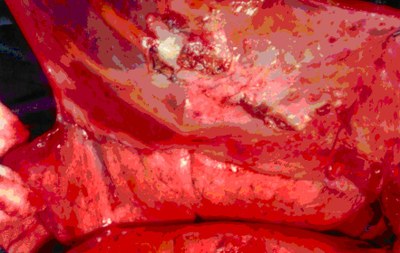

Posizionamento di protesi pericardica con fenestrature